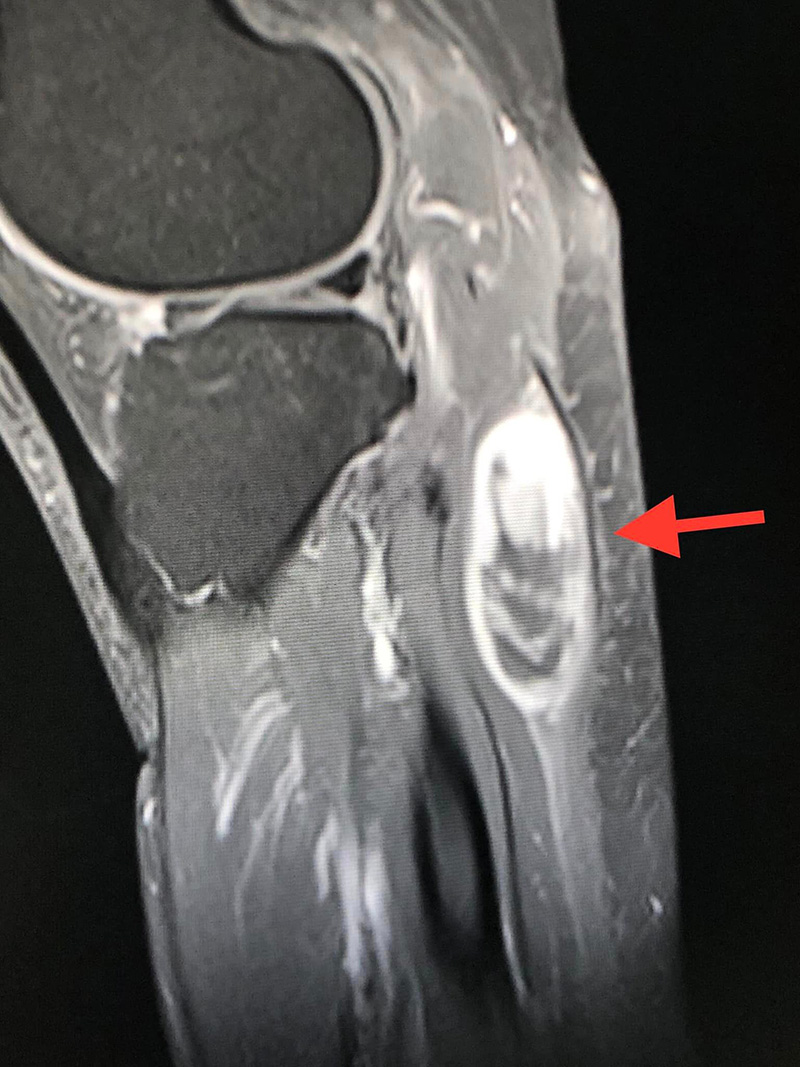

ภาพเคสตัวอย่างของ ผู้ป่วยหญิงวัย 61 ปี กับขั้นตอนการรักษา จากวันที่ตรวจพบก้อนเนื้อร้าย จนปัจจุบันหายดีแล้ว

- เดือนมีนาคม 2565 ทำ MRI ตรวจคลื่นแม่เหล็กไฟฟ้า พบก้อนขนาด 3.5 x 2.2 x 5.1 เซนติเมตร อยู่ชั้นใต้ผิวหนังติดกับกล้ามเนื้อของขา สงสัยมะเร็งเนื้อเยื่ออ่อน (soft tissue sarcoma)